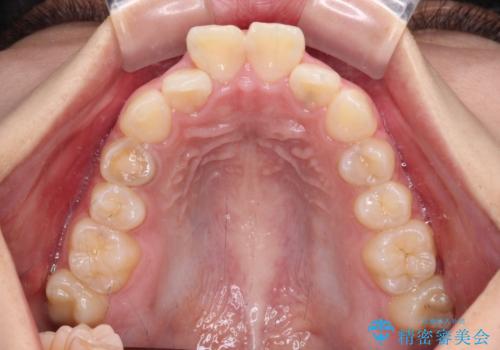

- 下唇の上に乗っかってしまうくらい前歯が飛び出していることを気にして来院された患者様です。

唇を閉じようとするとオトガイ部に力が入ってしまい、うまく閉じることができない状態であったため、上下左右の第一小臼歯4本を抜歯して、ワイヤー装置にて矯正治療を行うこととしました。

飛び出した前歯はしっかりと引っ込み、横顔の印象が大きく変化しました。